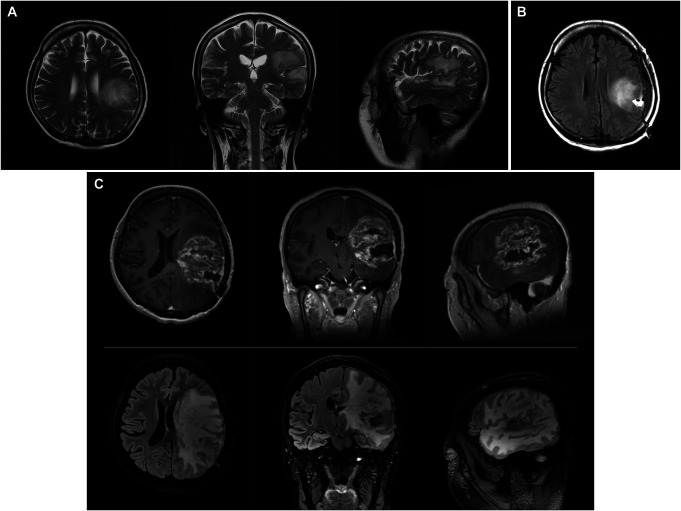

Clinical presentation: A 50-year-old, right-handed woman presented with recurrent glioblastoma invading her left superior temporal gyrus and inferior parietal lobule. She had severe aphasia, as she could barely verbalize her own name. However, we noticed that she could sing nursery rhymes with simple melodies and applied her singing ability as an axis of awake surgery. During awake surgery, she continuously sang simple songs to detect language dysfunction. As a result, 90% of the tumor was resected, preserving her language function and allowing for improvement. She was discharged 9 days after surgery without further neurological deterioration.